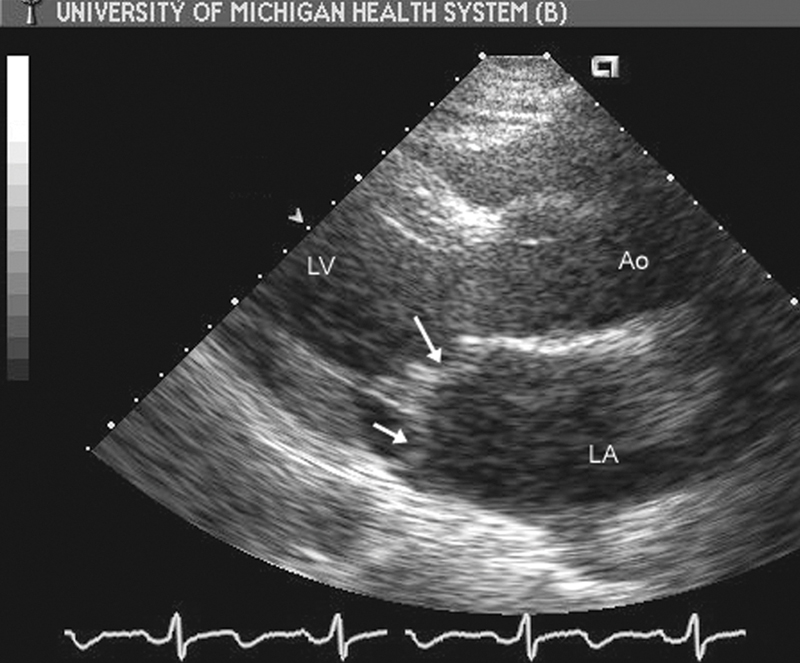

فحوصات تشخيصية لبعض امراض القلب والشرايين التاجية